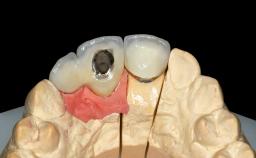

Replacement of Teeth 12 and 13 with Tissue-Level Implants

Type of Implants One-Piece|Reduced-Diameter

Abutment Type Customized

Prosthesis Type FDP